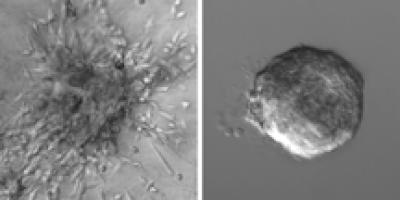

To sort out the contributions of both the genetic changes and the environment, Ewald's team separated tumor cells from their surroundings by taking fragments of human breast tumors and embedding them in two different commercially available 3-D gels, one that mimics the protein meshwork surrounding healthy mammary tissue and another that mimics tumorous mammary tissue.

The gels are tools often used to study tumor invasiveness. The first was made of proteins that normally create a thin layer around healthy breast tissue, acting as a molecular boundary for it. The second was made entirely of a protein, collagen I, which is found in unusually high concentrations around breast tumors.

If cancer cells are driven to disperse solely because of the genetic changes they carry, the researchers expected to see the tumor fragments behave similarly in both the healthy and tumorous environments. What they saw instead, says Ewald, was a distinct difference. As expected, 88 percent of tumor fragments sent cells crawling into the tumorous meshwork environment, the first step in metastasis known as dissemination. (See video: http://www.cellimagelibrary.org/images/42161 ) But only 15 percent of tumor fragments sent cells crawling into the normal environment. (See video: http://www.cellimagelibrary.org/images/42160 ) According to Ewald, these results indicate that the environment around a tumor plays a more direct role in cancer spread than previously thought.

If indeed cells can be enticed outward by the protein environment, the researchers reasoned, that environment might even be powerful enough to coax cells away from healthy breast tissue. To test this idea, they took fragments of both healthy and cancerous mouse mammary glands and placed them in the collagen I gels mimicking a tumor's environment. Results show that in the tumorous environment, nearly as many of the healthy fragments sent cells dispersing as did the tumorous fragments. (See videos: http://www.cellimagelibrary.org/images/42151 and http://www.cellimagelibrary.org/images/42152 )